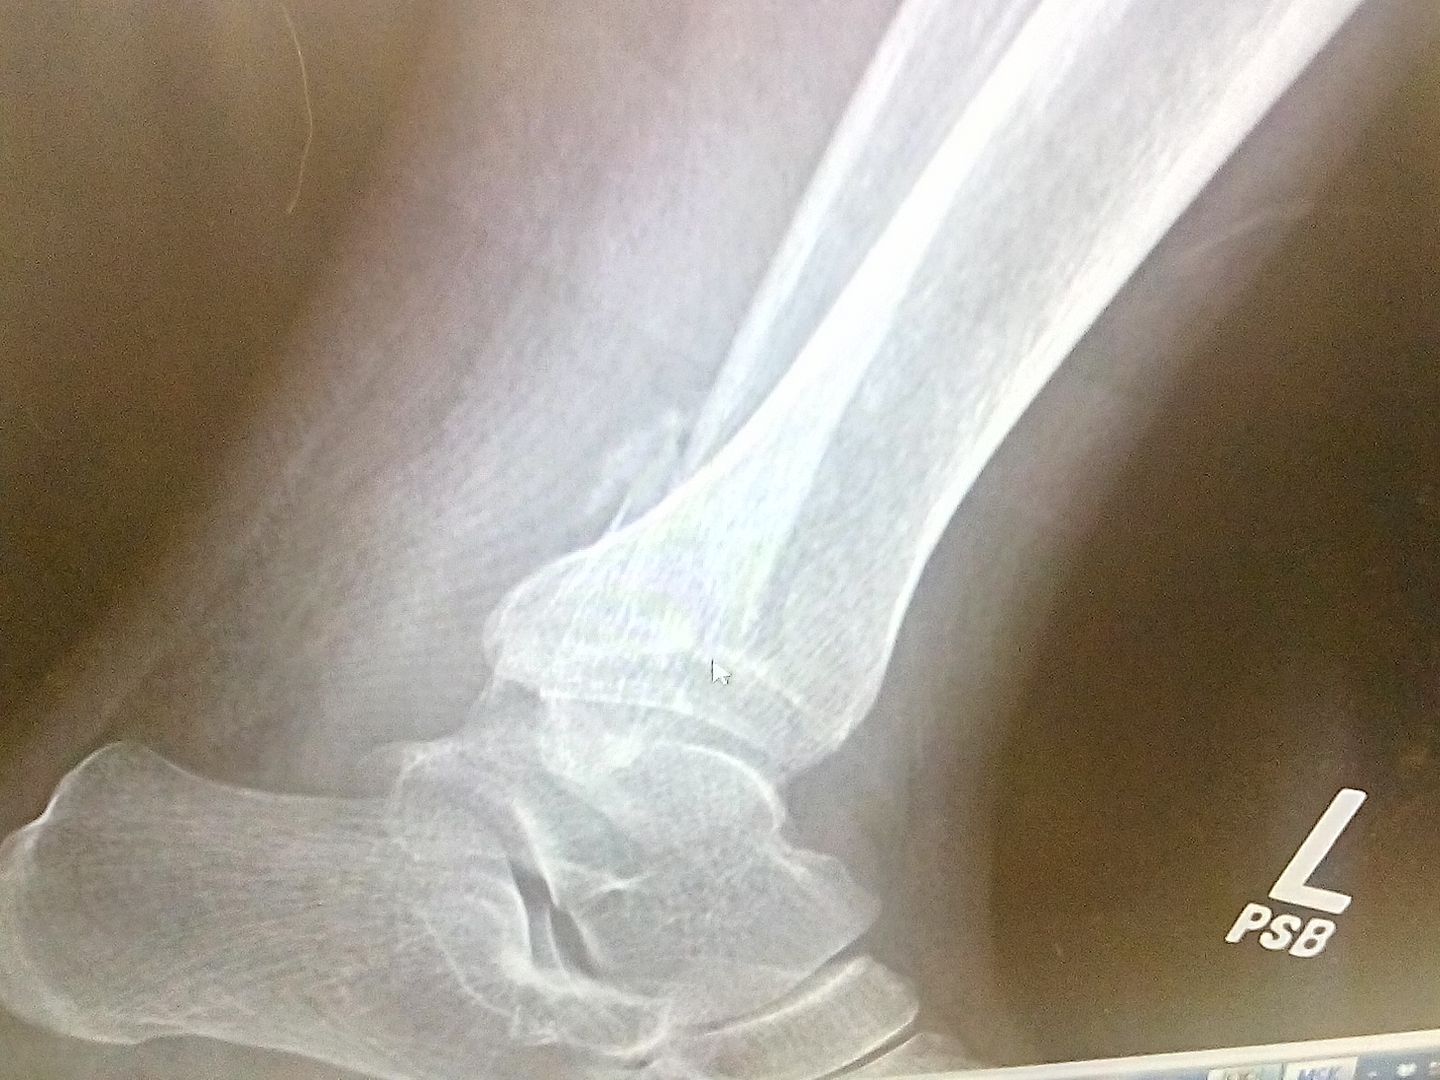

Medial inferior articular facet, near the talus dome?  Medial malleolus and deltoid looks fine, no sublux.  You pronated with external rotation? Can't see the effusion without a lateral view.

Heres the next project for the ortho